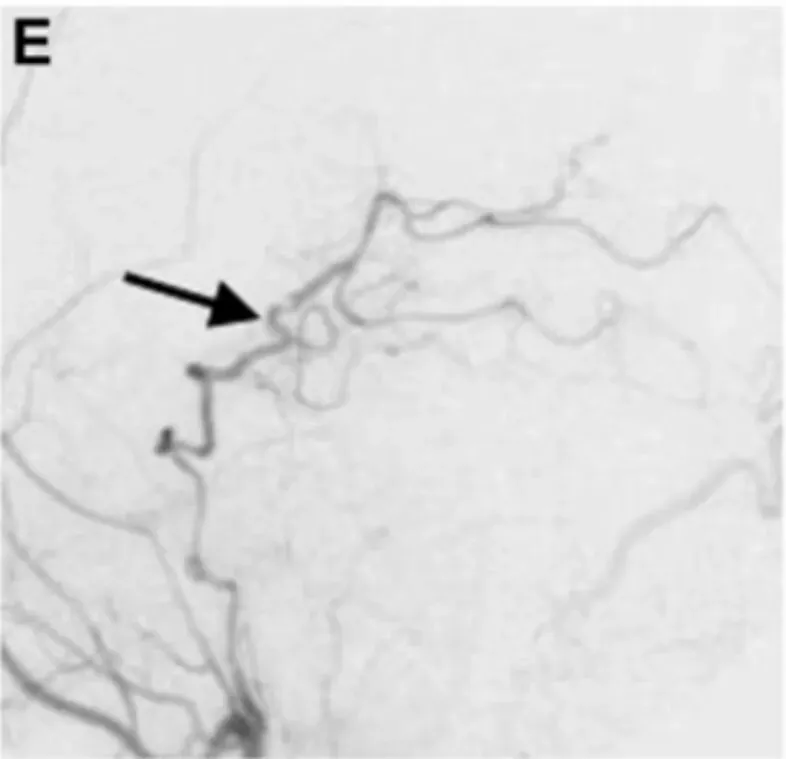

18天后真相终于明朗。延迟血管造影显示患者左侧P1-P2段存在正在生长的夹层动脉瘤,并呈现狭窄特征。此时医疗团队才真正"锁定"威胁生命的病因。

确诊后第20天,川岛教授团队决定为患者实施手术。此时动脉瘤已延伸至P2段后部,病情更加复杂。

手术方案极为精细:经左颞颞下入路实施动脉瘤孤立术和STA-PCA搭桥重建手术。手术过程中,川岛教授首先夹闭动脉瘤近端部分,同时谨慎保留丘脑穿支动脉——这些细微血管一旦损伤将导致严重后果。

随后,川岛教授选择PTA作为受体动脉,实施STA-PTA旁路手术,相当于在阻塞血管旁搭建"新桥",确保脑部供血不受影响。最后才将远端夹子放置于夹层动脉瘤上,同时保留穿支血管。

术后一周血管造影结果显示:通过旁路到达左侧PCA区域的血流良好,动脉瘤完全被排除。两周后患者出院回家,未出现任何神经功能缺损。